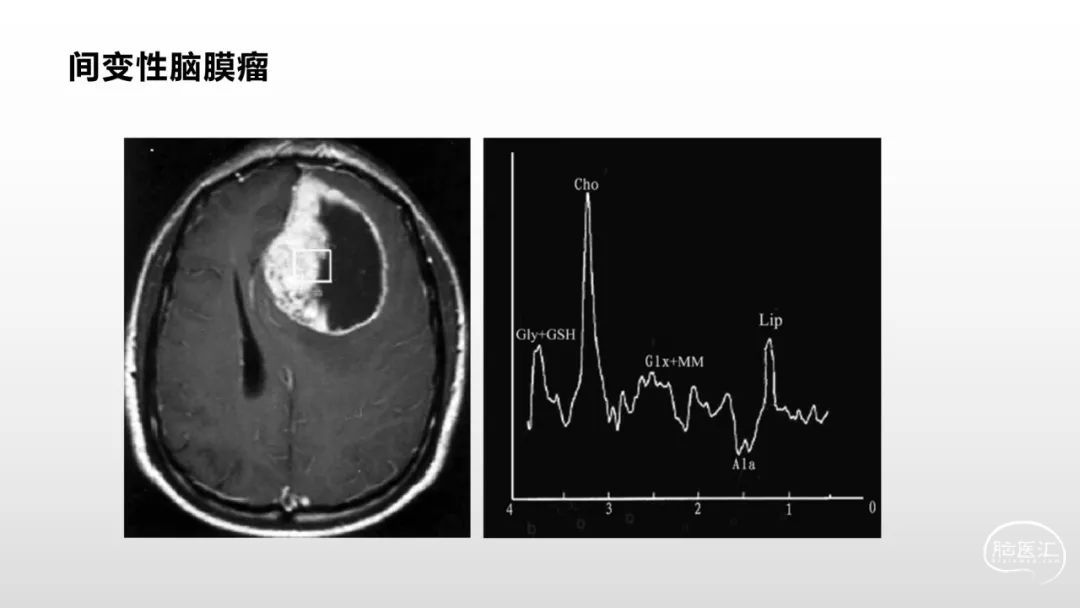

颅脑影像诊断基础知识讲座:脑膜病变